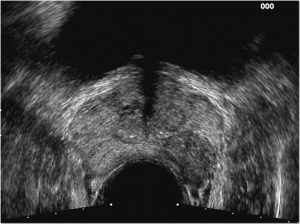

Pur con i continui progressi tecnologici che aiutano il medico nella diagnosi sempre più precisa e precoce delle patologie, l’esplorazione digito-rettale, (esame della prostata con il dito nel retto)

ci suggerisce un’idea molto precisa del volume, della consistenza e dei rapporti della ghiandola. Un ulteriore ausilio sia della valutazione volumetrica che dell’eventuale presenza di noduli sospetti di malignità è dato dall’ecografia transrettale. L’ecografia sovrapubica è utile invece per valutare sia il residuo post-minzionale, ossia la quantità di urina che avanza in vescica dopo la fine della minzione, sia lo spessore della parete della vescica stessa che si ipertrofizza in seguito allo sforzo che deve esercitare per potersi svuotare talvolta “sfiancandosi” al punto tale da determinare estroflessioni della mucosa dette diverticoli. Per poter avere una conferma o una smentita del fatto che la IPB determini ostruzione o meno si esegue la uroflussimetria. Tale semplice esame, che consiste nell’urinare in una apparecchiatura collegata ad un computer, consente di evidenziare il grado di ostruzione, la risposta a determinate terapie e soprattutto ci indica i casi in cui si debba intervenire chirurgicamente per risolvere l’ostruzione. Nell’utile esame delle urine spesso si evidenziano leucociti, batteri o globuli rossi (microematuria) quando sono presenti complicanze infiammatorie o infettive. Dagli esami ematochimici può essere evidenziata una insufficienza renale (innalzamento della creatininemia e dell’azotemia) qualora il grado di ostruzione raggiunga livelli davvero elevati. E’ importante evidenziare il fatto che obbligatoriamente dai 45-50 anni in poi, una volta all’anno, è necessario eseguire un controllo ematologico del PSA (Antigene Prostatico Specifico). L’innalzamento di questo valore potrebbe ricondurci ad una patologia maligna della prostata, anche se lo stesso può aumentare, più frequentemente nel giovane sessualmente attivo, a causa di patologie flogistiche della ghiandola o per un volume molto grande della stessa. Il suo innalzamento ci obbliga all’esecuzione di esami supplementari